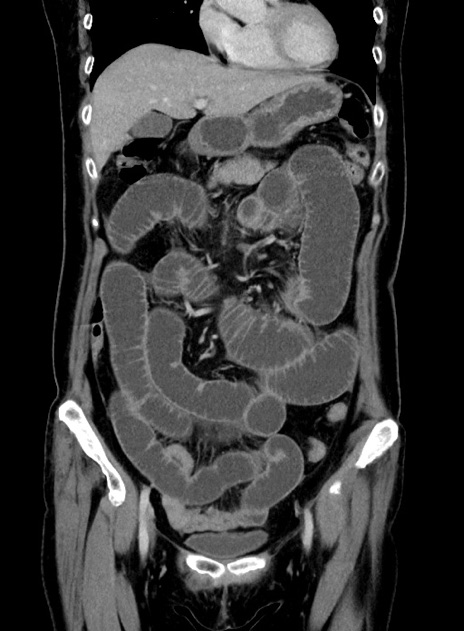

横断像

症例9(冠状断像)

【症例】 60歳代女性

【主訴】むかつき、みぞおちの痛み

【現病歴】3日前よりむかつきがあり、食事がとれない。

【既往歴】糖尿病

【身体所見】発熱なし、心窩部圧痛軽度あるも、腹膜刺激症状なし。

【データ】WBC 7400、CRP 1.92